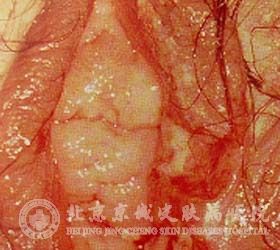

白塞病目前是一种多因素综合性所引起的自身*性病症,它主要细小血管炎为病理,外生殖器、口、皮肤溃疡为主要表现的慢性进行性复发性多系统炎症性病症。白塞病的症状表现如下所示:

1、皮肤病变:关节有红斑,多见于下肢,好发于腿部前面伸侧,有时也可出现于后面屈侧及大腿、臀部和上肢等处。红斑直径为1-5cm,呈鲜红色,圆形或椭圆形结节,有时数个结节融合成大的肿块。约2-3周后,结节由鲜红速变暗红,逐渐消失,结节部位常有时常出现水肿。